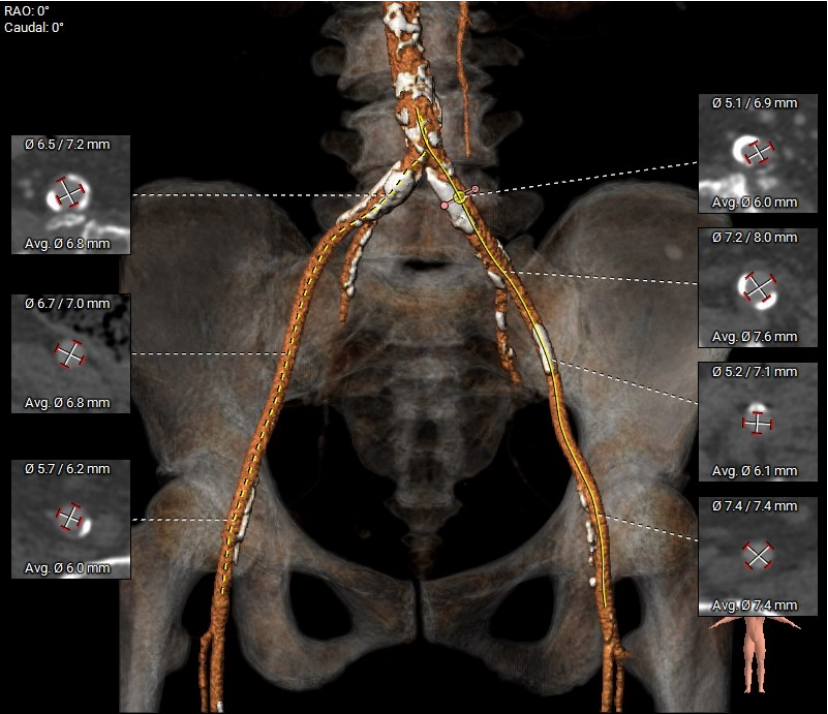

CT评估

收缩期瓣环:70.3mm

收缩期流出道:72.2mm

舒张期瓣环:68.1mm

舒张期流出道:73.1mm

左冠高度10.8mm

右冠高度14.1mm

主动脉窦宽:32.8mm、31.3mm、32.4mm

窦管结合部:113.9mm

升主动脉:146.6mm

制定策略

患者入路条件良好,三叶式主动脉瓣,主动脉瓣重度反流,流出道较短,STJ、升主动脉较大,瓣膜释放容易位移,瓣下1~2mm起始释放,最终锚定瓣下3mm。